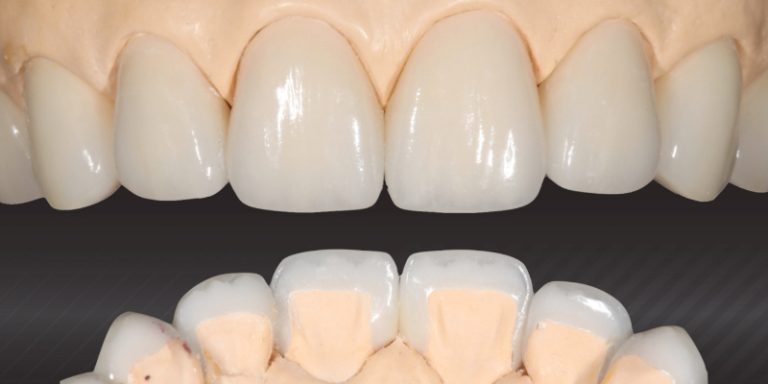

Technique for ‘Cementing’ and Retaining Conservative Ceramic Onlay Provisionals

Learn more about how indirect partial coverage ceramic restorations are becoming a mainstay of conservative restorative dental procedures.